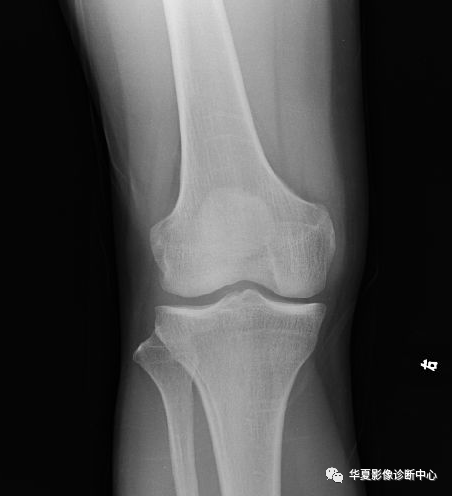

X线平片检查采用Kodak公司的CR成像系统,对患肢行正侧位投照。(图1-2)

骨信号的情况---隐性骨折在低场MRI表现为:T1WI序列上见由关节面向骨干走行的形态各异低信号区,有线状、条状、紊乱低信号,信号强度不均匀;与T1WI低信号改变相对应部位在T2WI上表现为相应形状的高、低混杂信号,且部分低信号周围可见高信号水肿改变。STIR序列图像上病灶呈显著高信号,与信号被抑制的临近正常骨髓形成鲜明对比,分界也较T2WI成像更为清楚。隐性骨折主要病理学改变为骨小梁断裂,无骨皮质中断,并伴有局部骨松质内水肿和出血。无骨皮质中断,尚不足以引起X线衰减系数的明显改变,X线平片无异常征象;CT在显示骨皮质及软组织异常方面明显优于传统X线,特别是三维重建能够有效的评价复杂骨折,骨外伤CT检查应用广泛,但CT对隐性骨折的显示亦极为有限。由外力作用使骨髓局部充血,毛细血管床过渡灌注而致骨髓水肿,水肿时自由水增加,一系列骨组织局部的化学成份变化导致了MRI驰豫时间发生变化,产生MRI信号异常改变。T2WI及压脂序列成高信号影,这信号改变代表着骨髓细胞外液的增多,而细胞外液的增多的程度和数量又决定着水肿所致异常信号的强弱和范围[4]。转组织抑制技术是MRI的一个重要性能,脂肪抑制技术在MRI应用中可以改善组织对比和增加病变显示机会,这样骨髓的脂肪抑制后就不会有任何信号,而隐性骨折线及骨髓水肿的异常高信号就会更加明显的显示出来。膝关节是全身中结构最复杂、最易受损的关节,外伤后常有长时间疼痛、不能负重。如果普通X线或CT检查未检出明显骨折,隐性骨折就容易被临床忽略,患肢若不给予制动,极易发展为明显骨折,或周围软组织的进一步损伤。而MRI其具有多参数、多序列、多方位成像、软组织分辨率高等特点,能清楚地显示膝关节隐性骨折的病变特点及严重程度,且其检查对患者安全,无辐射,因此,MRI检查对X线或CT检查不能解释的症状的患者是必须的,同时可作为定期随访的检查手段。